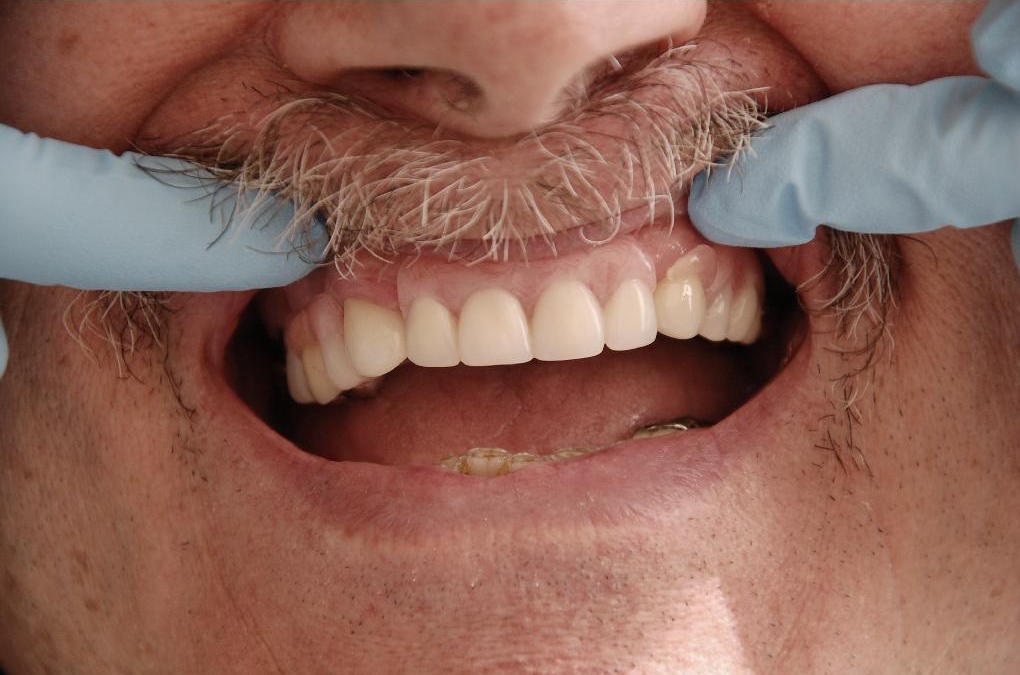

We provide a wide range of services to improve your smile. Treatments include teeth whitening, composite resin bonding, pink composites to shorten the crown length image, crowns, veneers, implants and Re-contouring of Enamel.

Crowns are an ideal restoration for teeth that have significantly broken or been weakened by decay or a large filling. A crown fits over the remaining part of the tooth, providing strength, shape, and color of a natural tooth.

Crowns and Bridges are usually made of porcelain and gold alloy. Porcelain is strong and is resistant to staining. Gold Alloy is used for its strength, hardness and durability. Gold alloy and porcelain are well tolerated by the gum and cheek – an allergic reaction is rare.